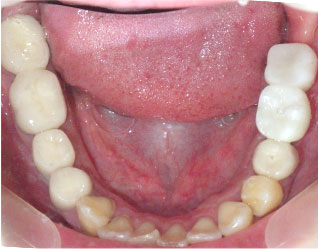

この方は向かって右側の上のブリッジが虫歯で外れかけていました。

また、右下と左上の奥歯が欠損していました。

まず右上のブリッジを外し、虫歯治療などしました。

それと並行してインプラントを骨に入れる手術を行いました。

インプラントが骨とくっつくまで3か月程度待つ期間がありますので

その間に虫歯治療や根の治療を完了させます。

インプラントが骨とついたら歯型を採って、インプラントに歯を被せます。

当院ではインプラント治療以外にも治療する部位がある場合、

インプラントと骨がつくために待つ期間を利用して他の歯の治療を進めますので

無駄な期間が無く、より短期間での治療が可能です。